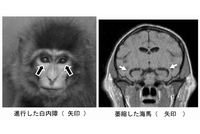

京都大学の正高信男教授らによる研究グループは、恐怖を感じる時の方が判断速度が向上することを明らかにし、恐怖感情を抱くことは認知情報処理を妨げるという、ここ一世紀の間信じられてきた心理学の定説を覆した。